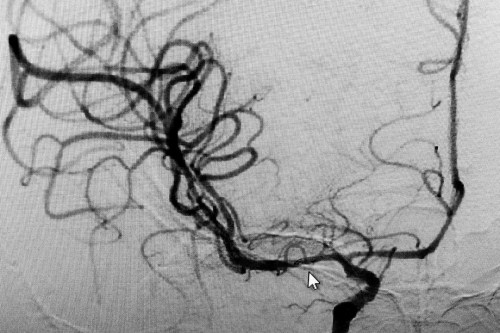

現(xiàn)在李振并主任成功將危險(xiǎn)解除,老姚術(shù)后恢復(fù)良好,家屬也松了一口氣。李主任告訴編輯:像老姚這么嚴(yán)重的情況,現(xiàn)在能恢復(fù)的這么好,可以說(shuō)是一個(gè)奇跡。再過(guò)一段時(shí)間,還會(huì)建議患者做支架植入(治療腦梗);颊哌@次是撿回了一條命,非常不易,希望把他以后能好好珍惜健康,不要再拿生命開(kāi)玩笑。

術(shù)后DSA血管造影:右側(cè)大腦中動(dòng)脈開(kāi)通,并且中度狹窄(光標(biāo)指向處)